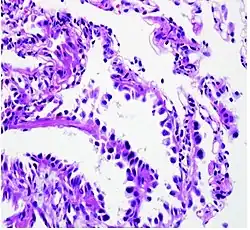

Histopathology of lepidic predominant adenocarcinoma.

• lepidic predominant[18]

Cell patterns identifying subtypes are associated with prognosis, ranging from favorable (lepidic) to intermediate (acinar and papillary) to poor (micropapillary and solid).[2]

Adenocarcinoma of the lung tends to stain mucin positive as it is derived from the mucus-producing glands of the lungs. Similar to other adenocarcinoma, if this tumor is well differentiated (low grade) it will resemble the normal glandular structure. Poorly differentiated adenocarcinoma will not resemble the normal glands (high grade) and will be detected by seeing that they stain positive for mucin (which the glands produce). Adenocarcinoma can also be distinguished by staining for TTF-1, a cell marker for adenocarcinoma.[29]

As discussed previously, the category of adenocarcinoma includes are range of subtypes, and any one tumor tends to be heterogeneous in composition. Several major subtypes are currently recognized by the World Health Organization (WHO)[1] and the International Association for the Study of Lung Cancer (IASLC) / American Thoracic Society (ATS) / European Respiratory Society (ERS):[30][31][32] lepidic predominant adenocarcinoma, acinar predominant adenocarcinoma, papillary predominant adenocarcinoma, micropapillary predominant adenocarcinoma, solid predominant adenocarcinoma, and solid predominant with mucin production. In as many as 80% of these tumors, components of more than one subtype will be recognized. Surgically resected tumors should be classified by comprehensive histological subtyping, describing patterns of involvement in increments of 5%. The predominant histologic subtype is then used to classify the tumor overall.[2] The predominant subtype is prognostic for survival after complete resection.[33]